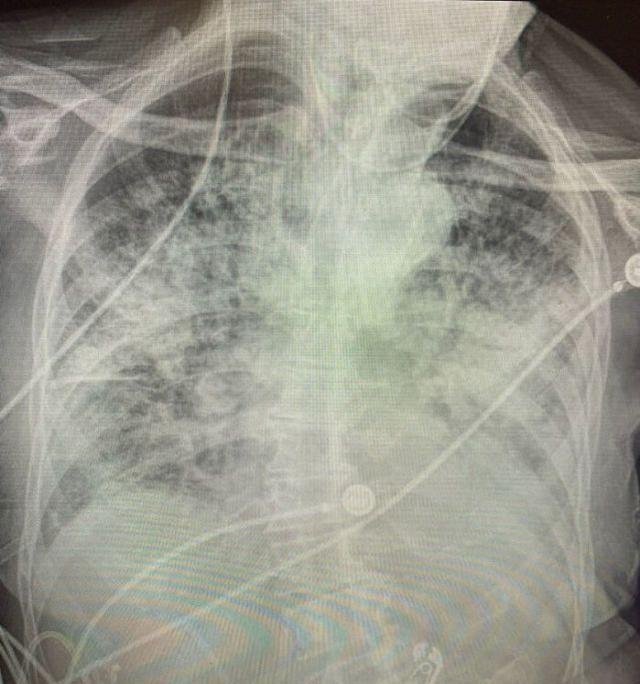

德克萨斯理工大学健康科学中心助理教授布列塔尼·班克黑德·肯德尔博士,在社交媒体上分享了确诊冠状病毒者的肺部的情况,并说:“比她见过的任何一种可怕的吸烟者的肺部都差”。

医生发布了三张肺部X光的照片,其中一名健康患者,一名吸烟者和一名COVID-19患者,以指出差异。

感染冠状病毒后肺部几乎呈白色,肺部已严重受损。

这些照片在社交媒体上获得广泛关注后,她说:从X射线比较可以看出,感染冠状病毒后的肺部看起来比吸烟者的肺部更糟。

医生告诉媒体:“虽然有人说我很好,我没有任何问题,但你查看他们的胸部X光片后,你会惊讶地发现,要么你会看到很多白色的密集疤痕,要么会在整个肺部看到它。即使很多人还没有感觉,但并不意味着以后也不会遇到问题,即使无症状的患者,也有70%至80%的人肺部x光片不容乐观。”。